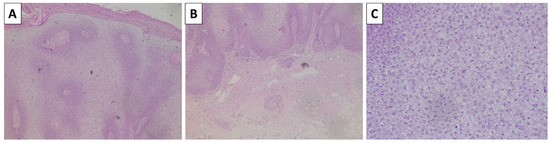

Figure 4.

Histopathology of the cheek lesion. (A) pigmented lesion in the superficial dermis, original magnification 40×; (B) higher magnification showing arrangement of the lesion in nests, original magnification 100×; (C) spindle cell melanocytes with subtle pigment deposition and a rim of sclerotic stroma surrounding the nests, original magnification 200×; staining (A–C) hematoxylin and eosin.